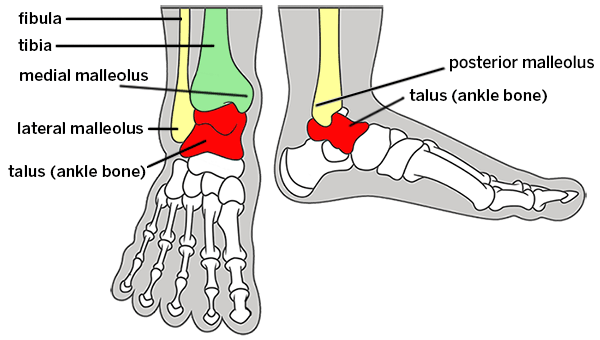

Ankle joint anatomy and arthritis

The ankle (known by doctors as the tibiotalar joint) is a complex joint that allows your foot to rotate and pivot in relation to your leg. Three separate bones meet to form the ankle joint. These are the:

- tibia (the larger bone in your leg)

- fibula (the smaller bone on the outside of your leg)

- talus (the bone that connects your leg to your foot)

Cartilage (cushioning) covers the ends of these bones to allow them to glide together smoothly. If the cartilage in the ankle becomes damaged or wears down due to injury or disease, the bone surfaces will rub each other during movement. This causes osteoarthritis (joint inflammation, or pain and swelling) in the ankle. Over time, the bone-on-bone grinding of osteoarthritis can wear away the bone surfaces, causing bone spurs and stiffness in the joint.